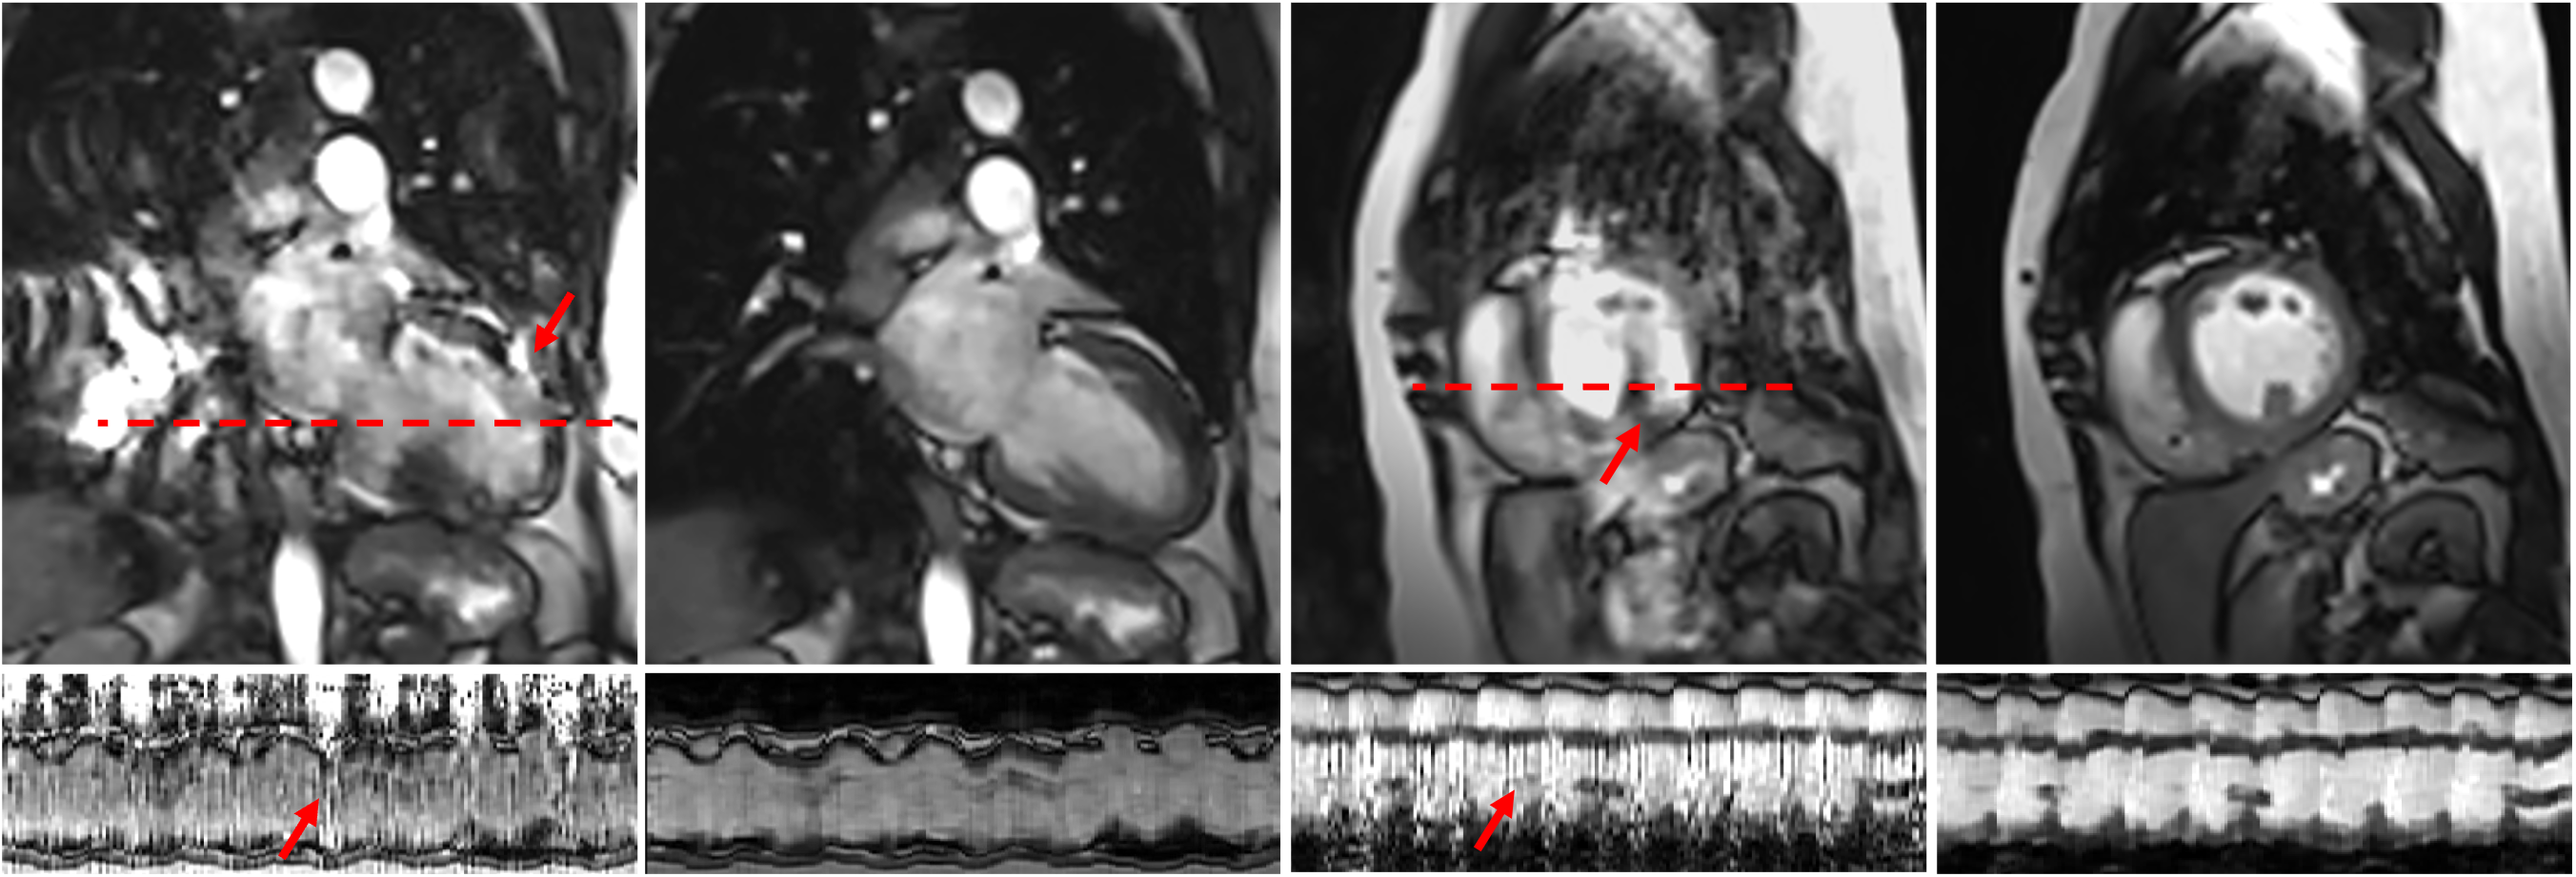

Refer to caption ABCD

Figure 8: Cine images from one of the patients without coil reweighting (A and C) and with coil reweighting (B and D). Strong motion artifacts are observed in A and C, which are effectively removed in B and D. The images at the bottom represent xx\mathrm{x}-tt\mathrm{t} profile along the dashed red line passing through the heart.